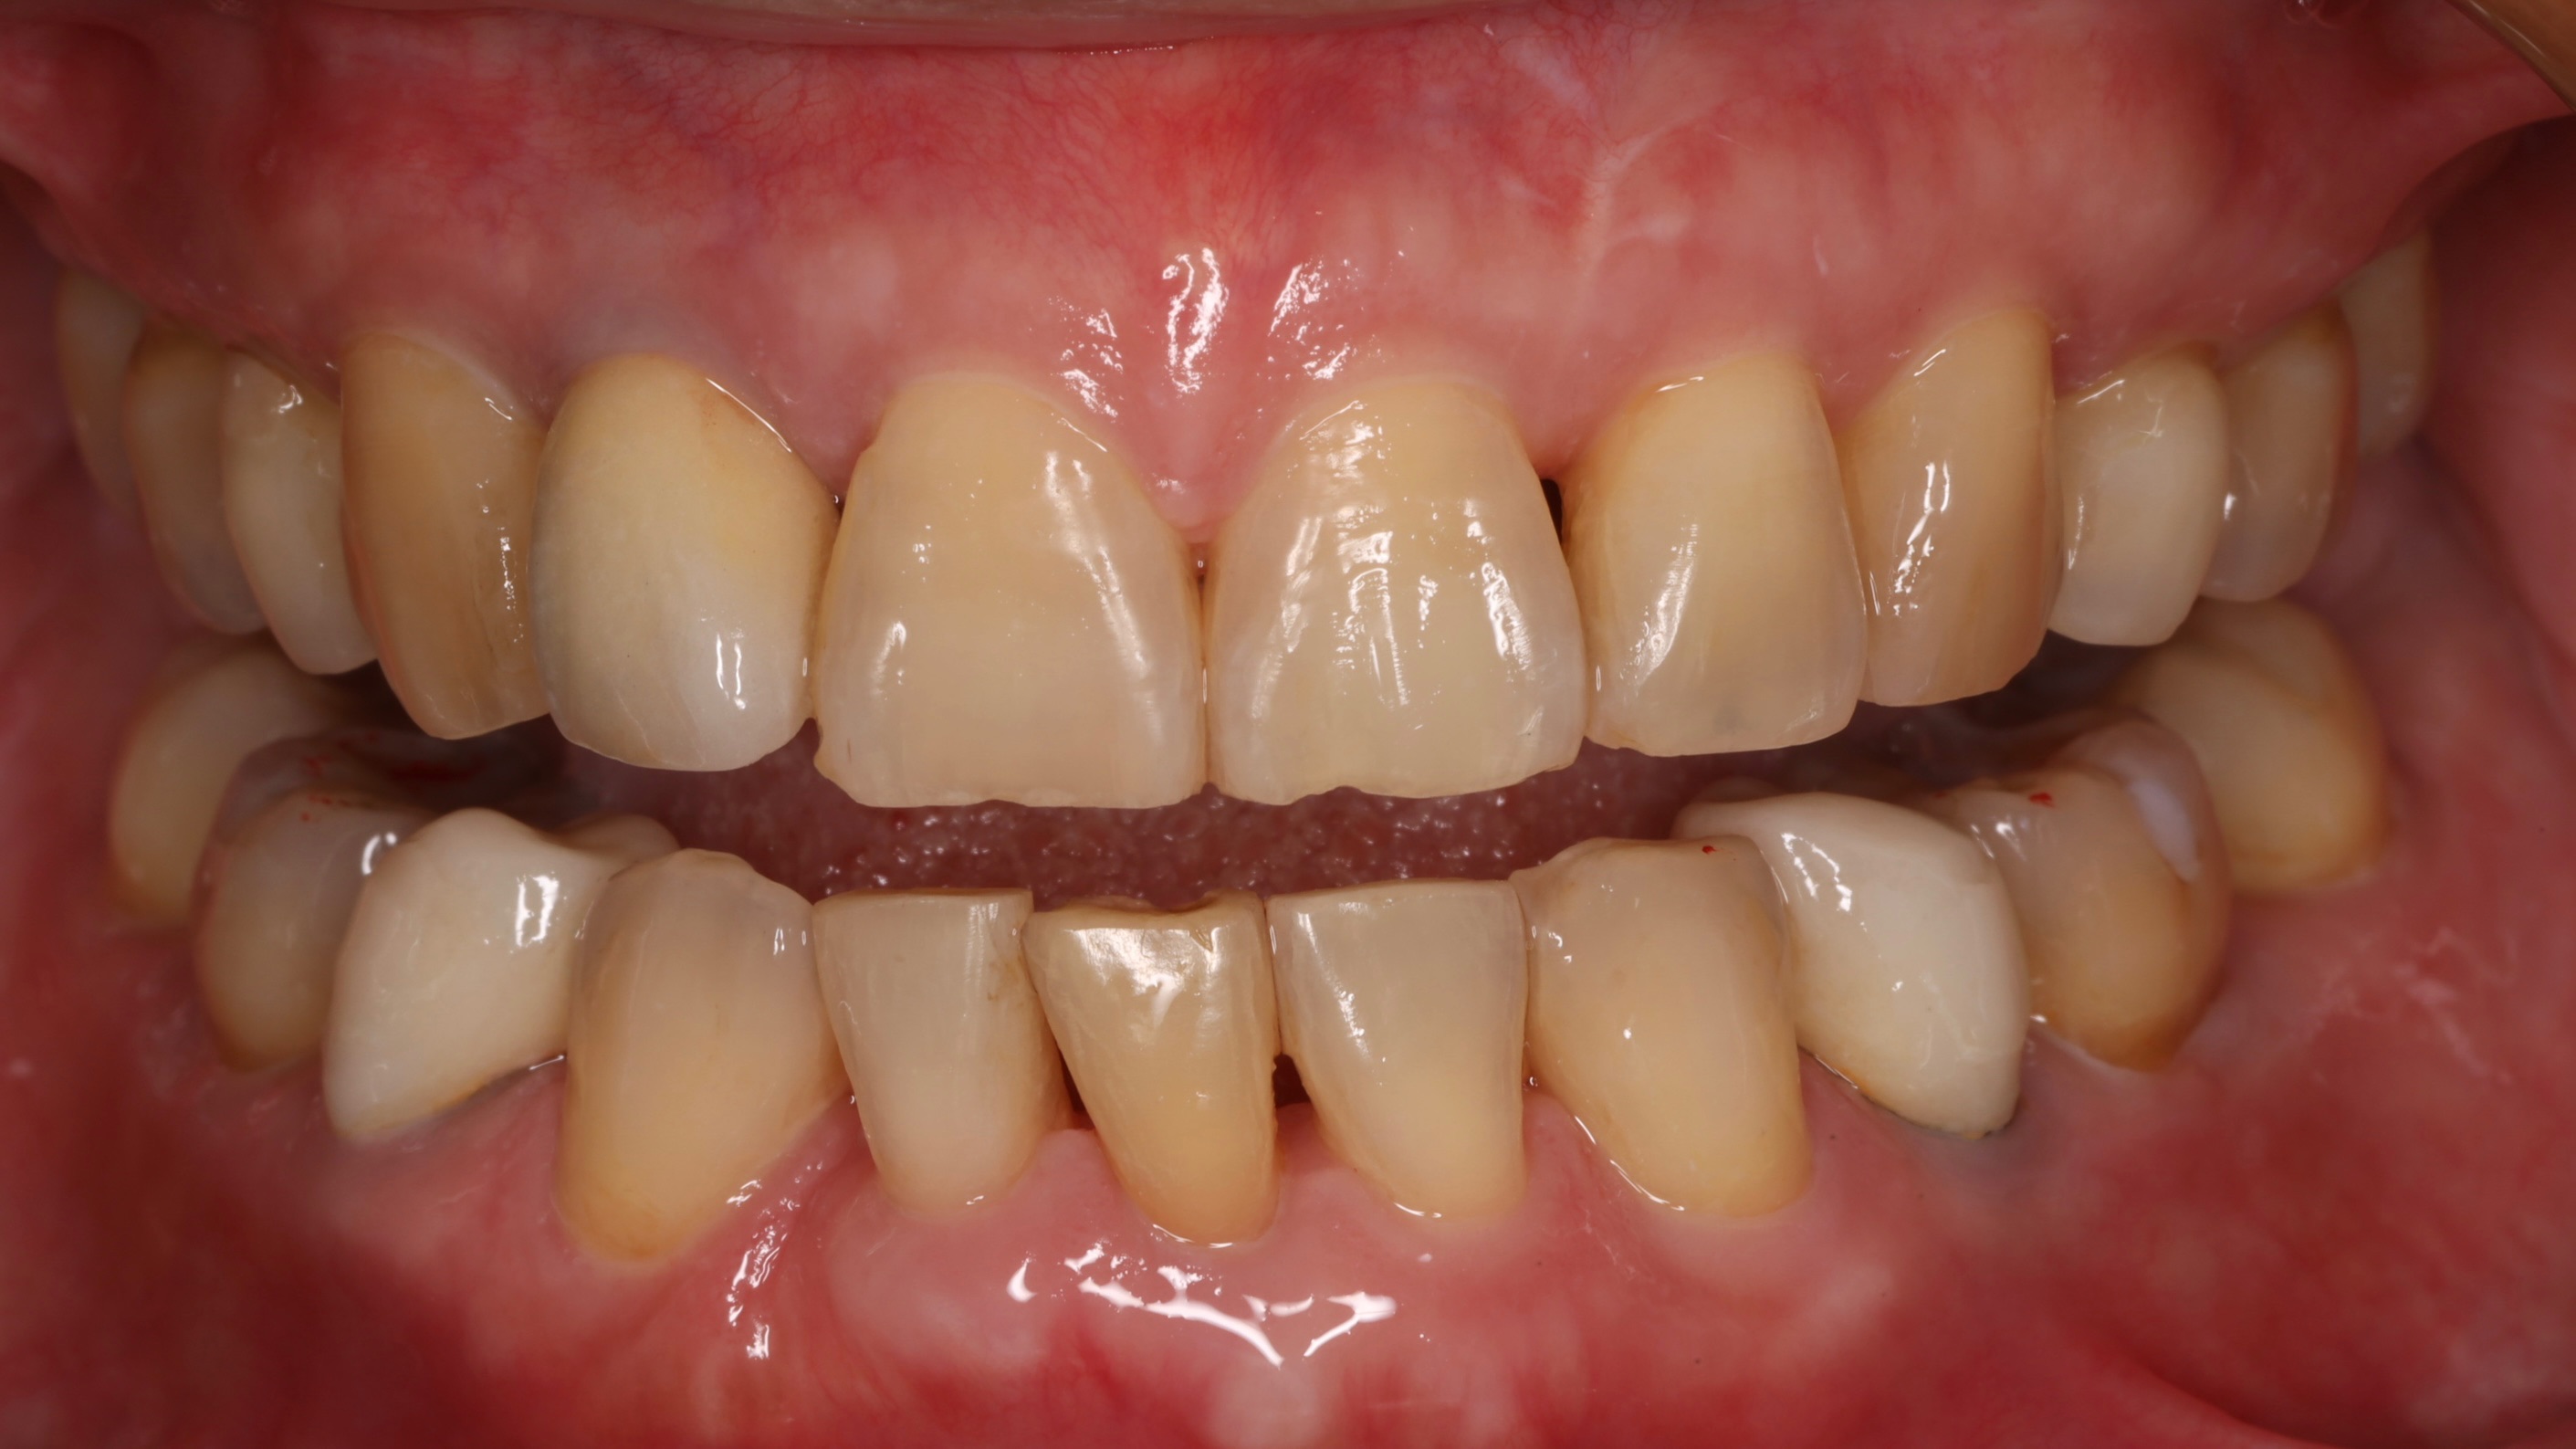

第四階段:隱適美矯正治療

等到補骨的部位完全癒合,骨頭和牙齦組織都恢復健康狀態後,我們便開始進行隱適美矯正治療,經過一年半的耐心治療,患者的牙齒排列變得整齊了,拔牙後的空間完美關閉,咬合功能恢復正常,日常清潔也變得容易許多。